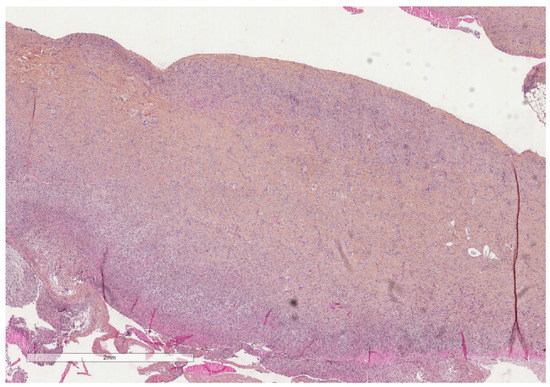

- Karpathiou, G.; Hathroubi, S.; Patoir, A.; Tiffet, O.; Casteillo, F.; Brun, C.; Forest, F.; Rahman, N.M.; Peoc’h, M.; Froudarakis, M.E. Non-specific pleuritis: Pathological patterns in benign pleuritis. Pathology 2019, 51, 405–411. [Google Scholar] [CrossRef] [PubMed]